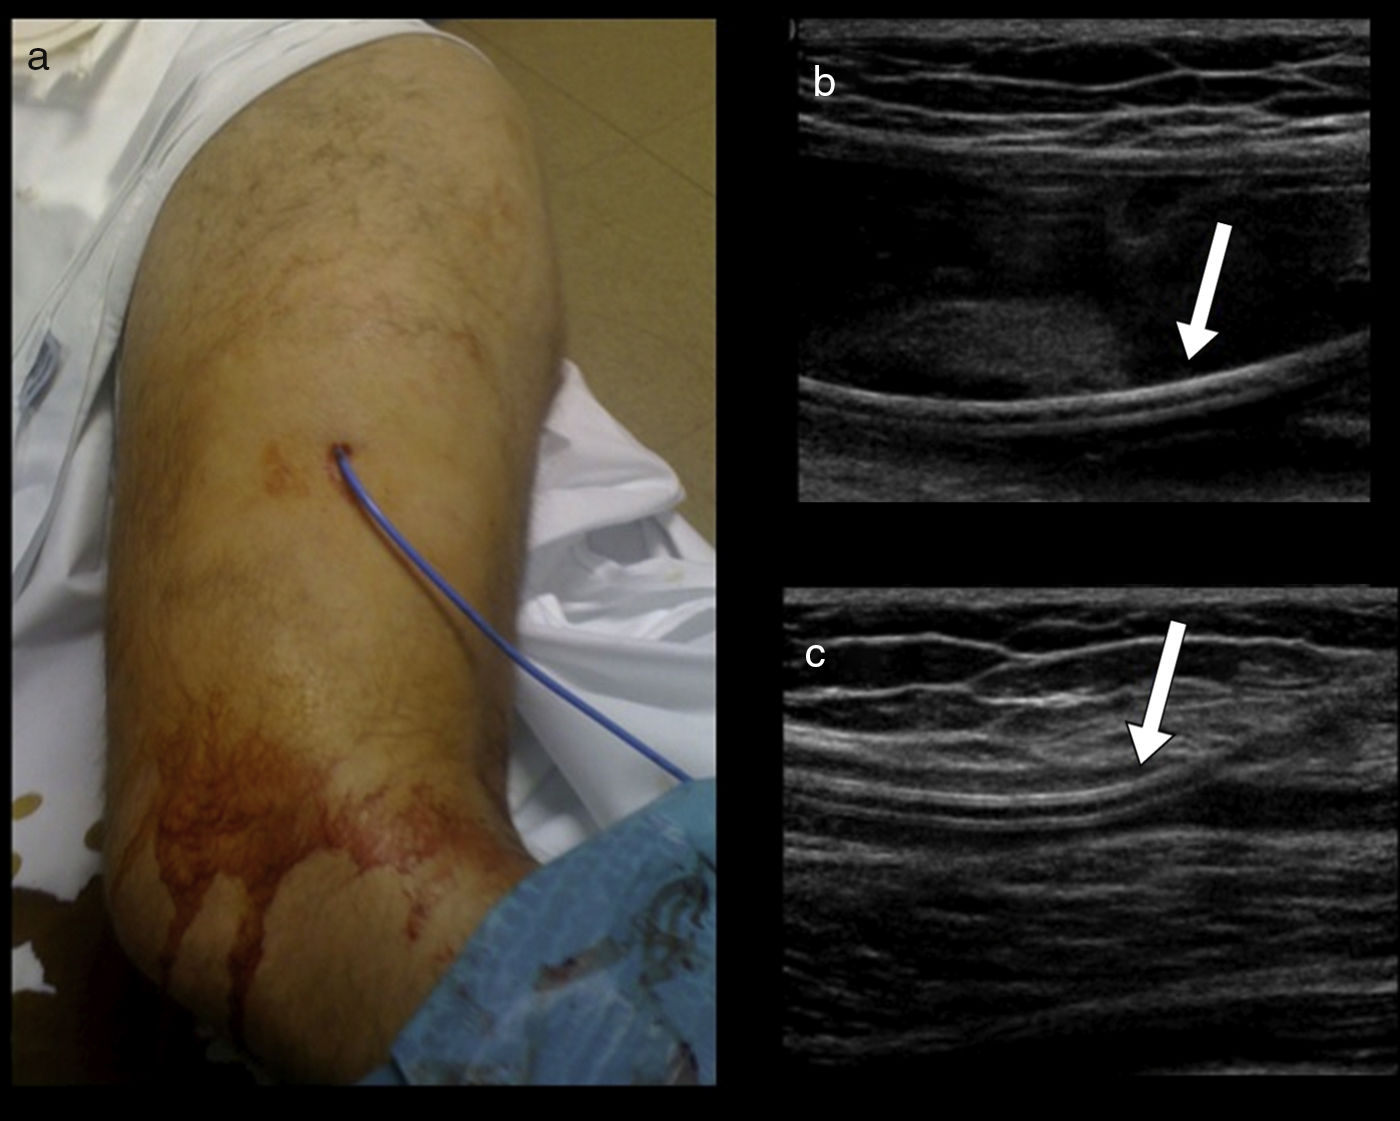

Material and methodsWe retrospectively reviewed 17 patients (11 men and 6 women; mean age, 56.1 years, range 25–81 years) diagnosed with Morel-Lavallée lesions in two different departments. All patients underwent ultrasonography, 5 underwent computed tomography, and 9 underwent magnetic resonance imaging. Percutaneous treatment with fine-needle aspiration and/or drainage with a 6–8F catheter was performed in 13 patients. Two patients required percutaneous sclerosis with doxycycline.

ResultsAll patients responded adequately to percutaneous treatment, although it was necessary to repeat the procedure in 4 patients.

ConclusionsRadiologists need to be familiar with this lesion that can be treated percutaneously in the ultrasonography suite when it is not associated with other entities.